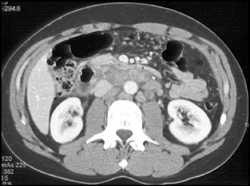

Diagnosis

Prominent Gastric Folds